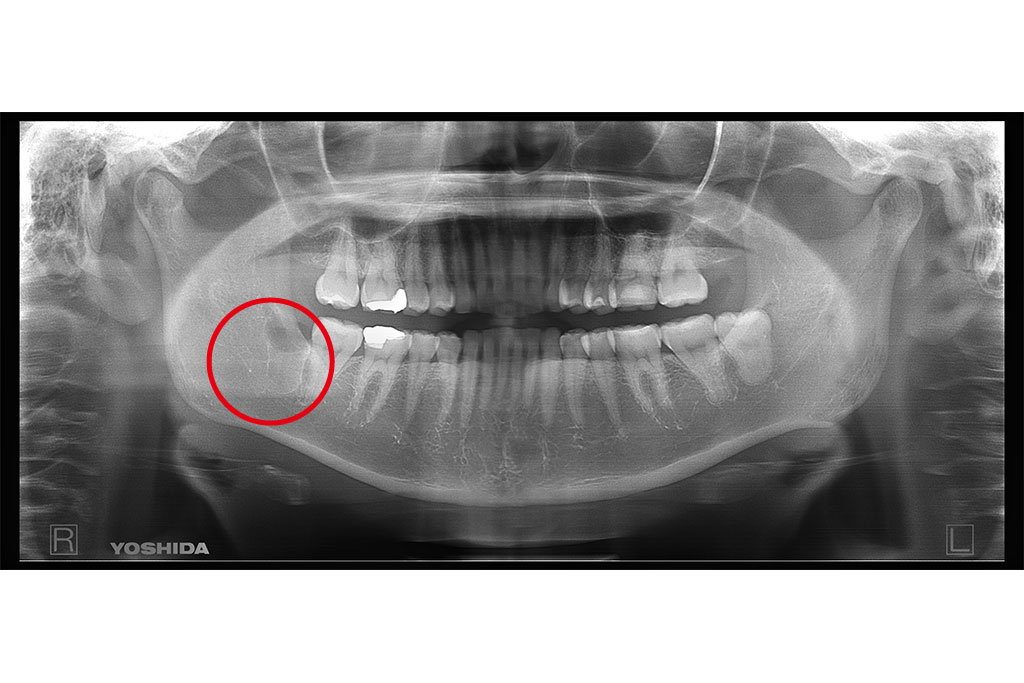

父のレントゲン写真と口腔内を見て、インプラントを入れる位置を一緒に決めて行きました。

右上は歯があるように見えて隣の歯につなげてある被せ物があるだけの状態です。

その右上は骨がないためサイナスリフトという処置を施した後にインプラントを入れる手術をしなければならないのですが、(サイナスリフトは骨を作るだけで6ヶ月待ちます。)

私は水口先生が開発したオステオプッシャーを用いて、骨がないところに骨を足す手術と並行してインプラントを入れる手術を施しました。

左側の入れ歯を入れていたと言っている場所には通常の方法でインプラント治療を、左上の奥歯2本は歯周病でグラグラだったため抜歯と同時にインプラントと治療を行いました。

左側のレントゲンがが最初の状態です。右側がインプラントを入れ、被せ物まで入れた状態のレントゲンです。